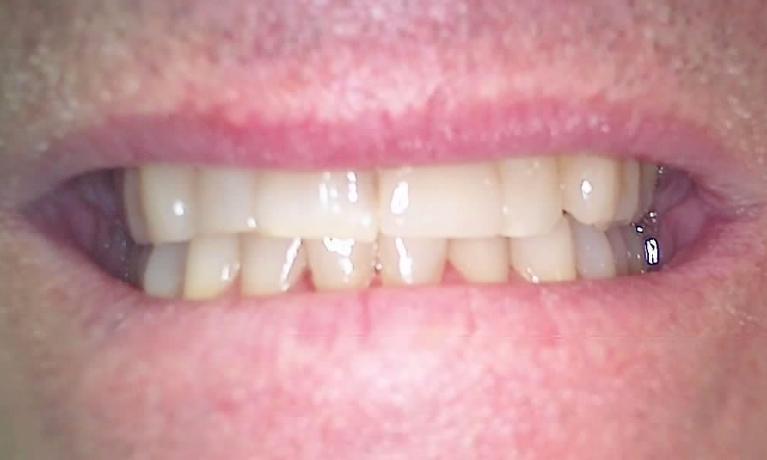

dental crowns | dental bridges | palos heightsCrowns and bridges are restorations that correct dental problems, while protecting and strengthening your teeth.

A dental crown is custom-made to fit over a damaged natural tooth. It restores the function of the tooth and provides strength and support. Dental bridges are also versatile and have a number of uses.

Crowns and bridges are usually made of porcelain because of its natural appearance and durability.

Everyone wants a smile that is healthy and beautiful, and we can help you reach that goal by using crowns and bridges. Updated techniques and treatments have made the placing of crowns and bridges easier than ever before.